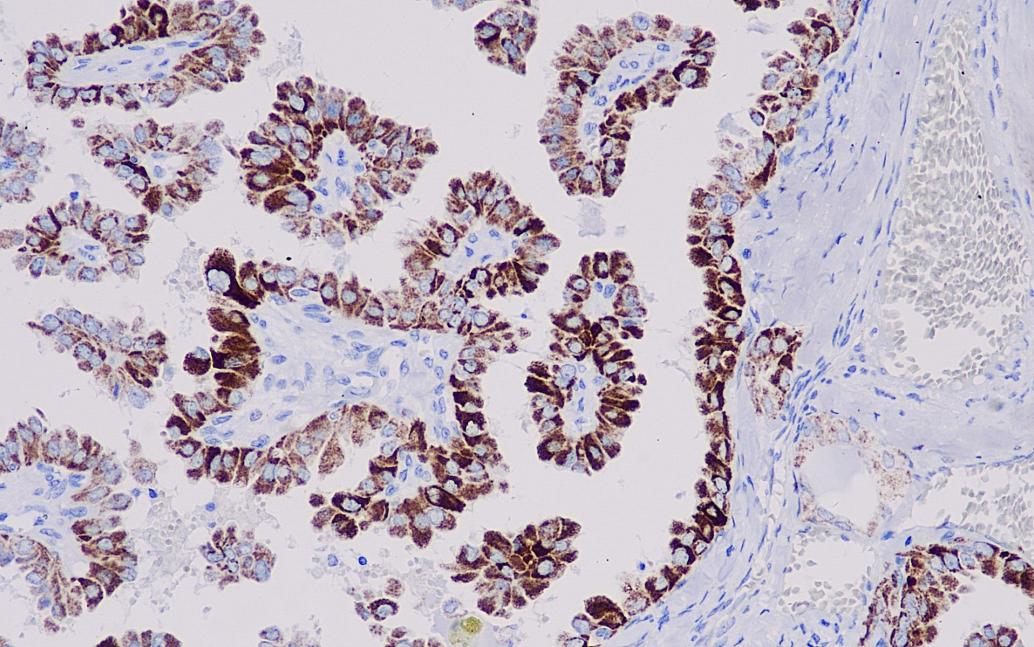

阳性对照: 甲状腺乳头状癌

BRAF基因是在尤文氏肉瘤中发现的。研究发现,BRAF V600E在黑色素瘤、甲状腺乳头状癌、多形性黄色星性细胞瘤、朗格汉斯组织细胞增多症、胶质瘤和结直肠癌等多种肿瘤阳性表达。目前多用于肿瘤和靶向药物的研究。

BRAF V600E抗体试剂可与BRAF V600E分子抗原特异性结合,含BRAF V600E抗体试剂的免疫组化试剂盒适用于黑色素瘤、结直肠癌、甲状腺乳头状癌等的精准诊断。